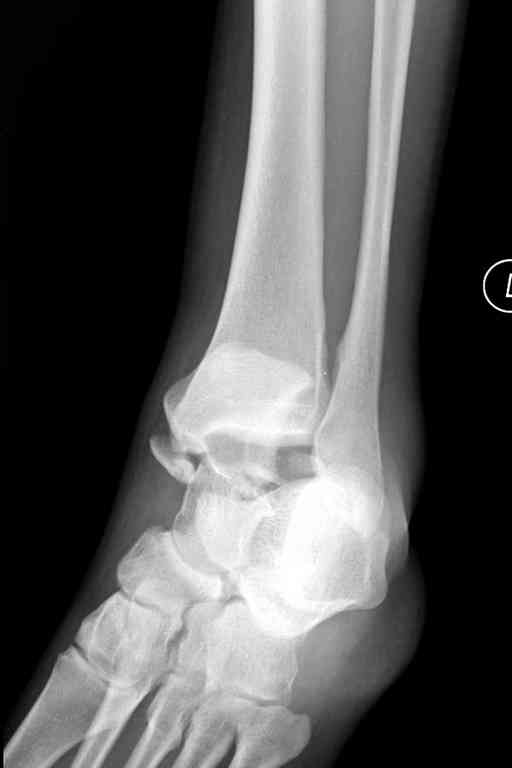

Второй случай прооперирован вчера.

10 дней назад поступил с открытым повреждением медиальной лодыжки и переломо вывихом таранной кости. Ургентно сделана репозиция с наложением наружного фиксатора + Irrigation&Debridment.

Во время репозиции выявили повреждение заднего сухожилия м. тибиалис и задней большеберцовой артерии. Медиальную рану удалось закрыть частично и установлен вакуум.